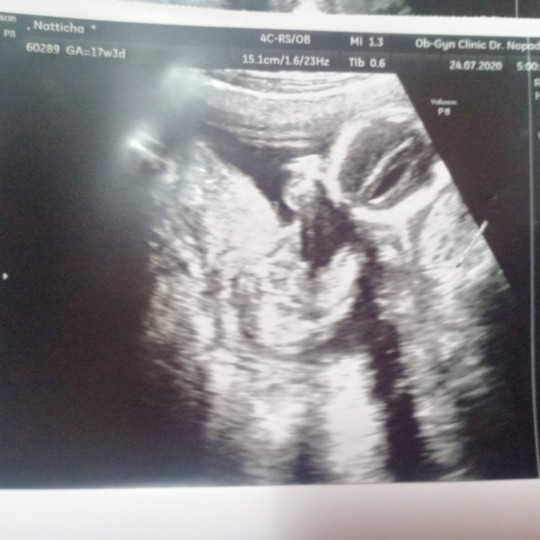

18W3d ลุกสาวจ้าา